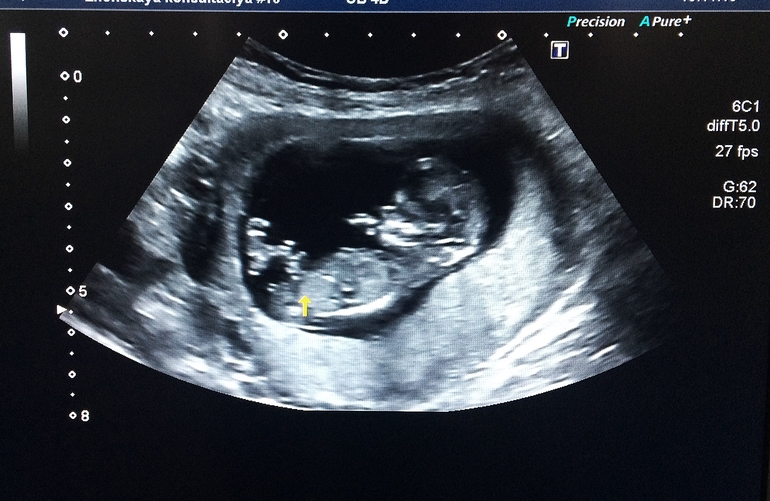

. Кровь будет готова через неделю, а от УЗИ я как-то большего ожидала...Прием вела не моя врач, а какая-то другая, бука( Ну да ладно, самое главное, что все хорошо, сердечко 167, все органы на месте, ручки- ножки показала, сердце, желудок и остальное) По УЗИ срок 12+3, прямо как по месячным. Крошка моя спала, так и не удалось разбудить, ленивчик маленький. Пол "бука" даже предполагать не стала, сказала "после 19 недель", моя врач на этом сроке хотя бы предположение делала (правда не правильно:-))). А мне не к спеху, я понимаю, что и мальчика, и девочку любить буду одинаково.

Хорошо бы девочка! Я этот снимок вдоль и поперёк иссмотрела, если этот прыщик- половой орган, тогда точно девочка, но это может быть, например, пуповина, тогда вполне может быть и мальчишкой)

Я поздно, наверное..)) но...это мальчик. я уже в этом ас) где 2 полосочки , это не пирожок, а какие-то помехи... А вот то, что чуть правее-видно: мошонка и перчик вверх...Пусть я ошибаюсь!

мнения разделились, скоро узнаем кто же у нас поселился) Но по-моему "две полоски" на помехи не похоже)

Карапузик:)!Может я ошибаюсь, но похоже на девочку,бородавочка прямо торчит, а у мальчиков образует угол в 30 гр. со спиной на таком сроке и торчит вверх.Кто-то давал ссылку на сайт там подробно все описано, как на таком сроке выглядит девочка и как мальчик!Мне на первом скрининге показали тоже вот такую бородавочку, но она больше вверх как стручок торчала, сказали что скорее всего у нас мальчик, вот в субботу узнаем на втором скрининге:))

http://www.baby.ru/blogs/post/28474745-25801154/ вот тут написано про определение пола, но все равно пока это все гадание на кофейной гуще

, я еще недели 4 буду в неизвестности. Я даже не уверена, что на этом фото именно половой бугорок)

в пн иду на узи,я не видела какого пола ваши детки,на фото с узи видно что наклон писюльки как должен быть у девочки